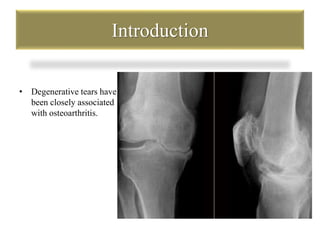

Introduction

• Degenerative tears have

been closely associated

with osteoarthritis.

Introduction • Degenerativetears have been closely associated with osteoarthritis.